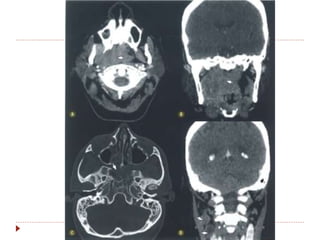

 Nasoangiofibroma juvenil

 Jovens masculinos com epistaxe

 Importante realce pelo contraste

 Localizado na fossa pterigopalatina, progredindo para

cavidade nasal, faringe e região infratemporal.

Nasofaringe  Plasmocitoma:  Massade partes moles ovoide, homogêneo, mucosa, com isossinal em T1 e hiperssinal em T2.  Nasoangiofibroma juvenil  Jovens masculinos com epistaxe  Importante realce pelo contraste  Localizado na fossa pterigopalatina, progredindo para cavidade nasal, faringe e região infratemporal.  Adenoma pleomórfico  mais frequentes no espaço parafaríngeo.